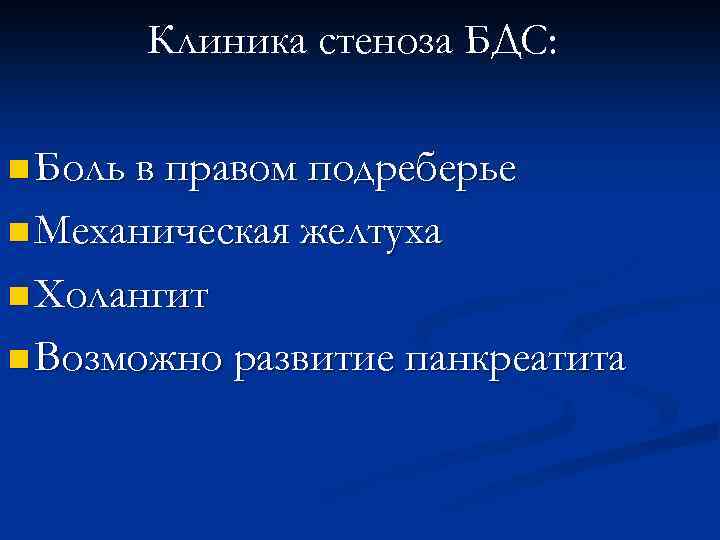

Клиника стеноза БДС: n Боль в правом подреберье n Механическая желтуха n Холангит n Возможно развитие панкреатита

Клиника стеноза БДС: n Боль в правом подреберье n Механическая желтуха n Холангит n Возможно развитие панкреатита